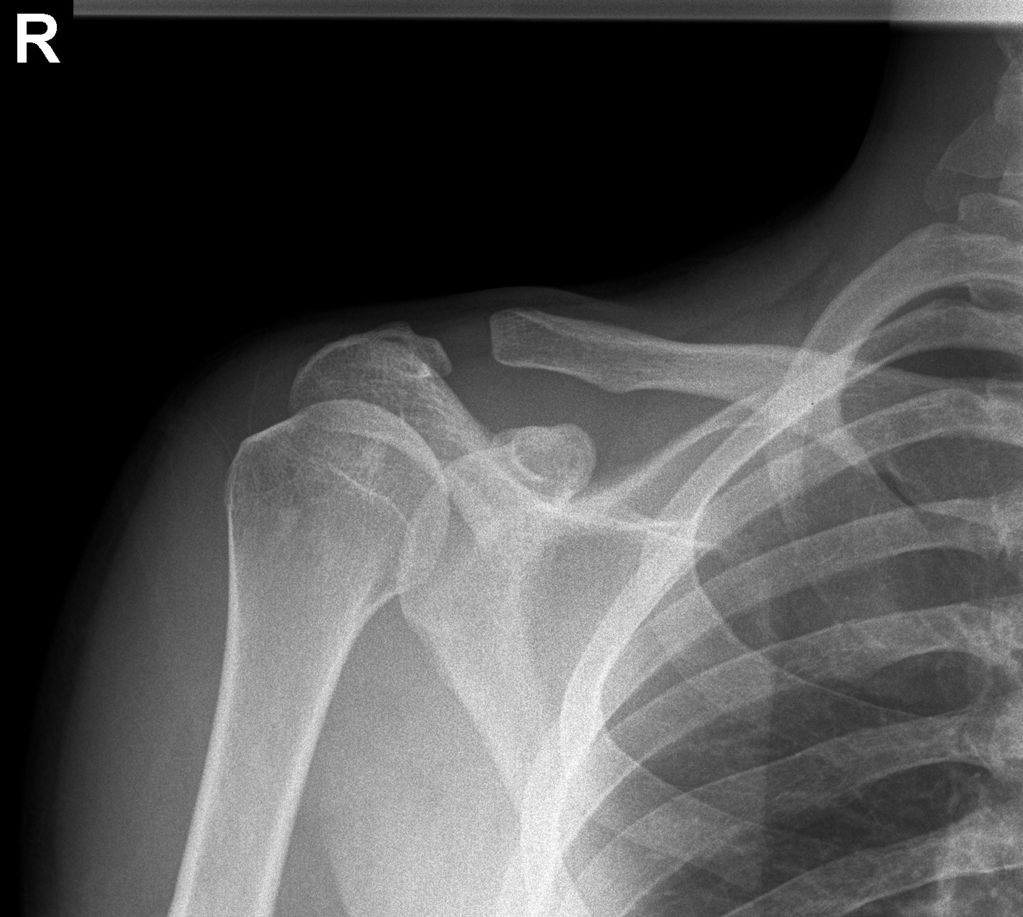

How To Help A Separated Shoulder . After that, physical therapy can help restore. understanding the causes and embracing the benefits of early diagnosis and separated shoulder treatment can help ensure a. So do what you can to reduce. people with persistent or severe shoulder pain may have a separated shoulder condition. a separated shoulder refers to an injury to the ligaments of the acromioclavicular joint (commonly known as the ac joint), which is the joint. After that, physical therapy can help restore. getting a separated shoulder or a dislocated shoulder is painful and debilitating. Nonsurgical treatments, such as a sling, cold packs, and medications can effectively help manage.